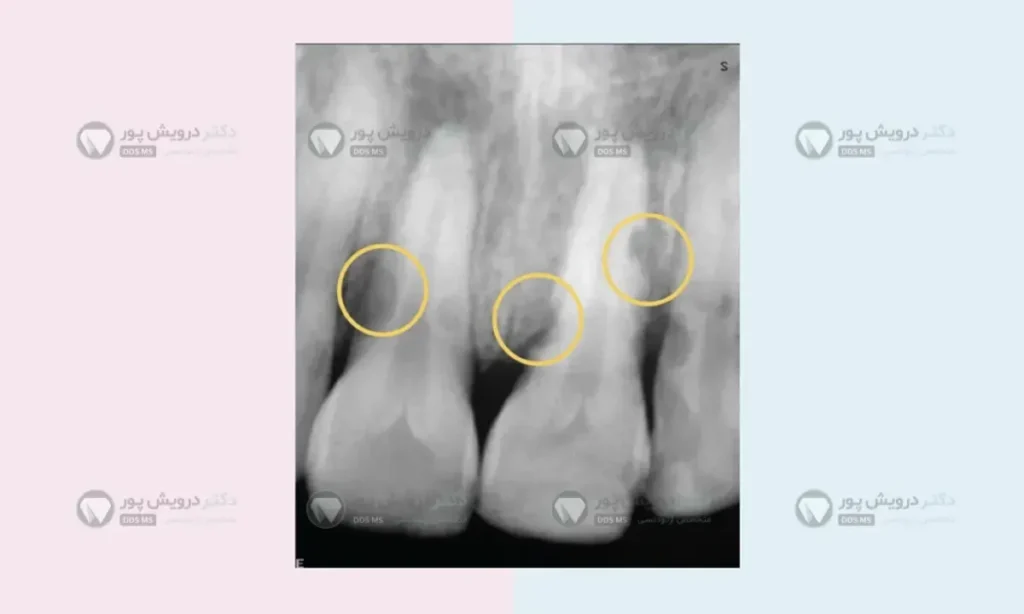

تحلیل رفتن ریشه دندان ها یکی از بدترین اتفاقات است

وقتی نیروها بدون محاسبات ریاضی و فیزیکی به دندان وارد شوند، بدن واکنش دفاعی نشان می دهد. سلول های استخوان خوار به جای اینکه راه را برای حرکت دندان باز کنند، شروع به خوردن خودِ ریشه دندان می کنند.

ما بیمارانی را دیدهایم که بعد از انجام ارتودنسی توسط افراد غیر متخصص، ریشه دندان هایشان به قدری کوتاه شده، که دندان دچار لقی است. اصلاح این وضعیت مثل راه رفتن روی لبه تیغ است چون هر حرکت کوچکی ممکن است باعث آسیب بیشتر به دندان شود.